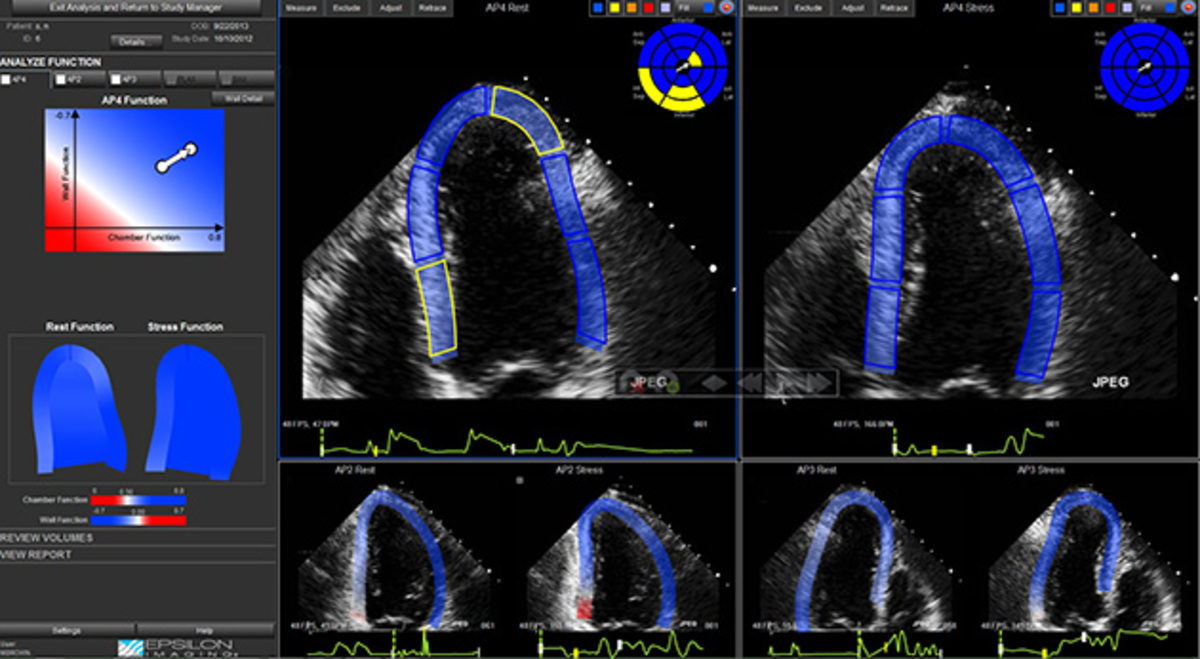

Για την πραγματοποίηση της δοκιμασίας, ίσως χρειασθεί να τροποποιήσει ή να διακόψει τη φαρμακευτική του αγωγή 24 – 48 ώρες πριν την εξέταση, ιδιαίτερα εάν λαμβάνει β–αναστολείς, πάντα σε συνεννόηση με τον καρδιολόγο. Η εξέταση ξεκινά με τη διενέργεια ενός υπερηχογραφήματος, όπου απεικονίζονται όλες οι καρδιακές δομές. Κατόπιν, χορηγείται σταδιακά το φάρμακο, μέσω ορού, σύμφωνα με προκαθορισμένο πρωτόκολλο, προκειμένου να προκληθεί ταχυκαρδία και αύξηση της δύναμης σύσπασης της καρδιάς. Κατά τη διάρκεια της εξέτασης λαμβάνονται τομές της καρδιάς, καταγράφεται η αρτηριακή πίεση και ο ρυθμός της, ενώ τα δεδομένα αποθηκεύονται στη μνήμη του μηχανήματος για μελλοντική χρήση. Ο χρόνος που απαιτείται για τη διεξαγωγή της εξέτασης είναι συνήθως 30 λεπτά, με μέγιστο χρόνο τη 1 ώρα, και το κόστος της καλύπτεται πλέον από τα ασφαλιστικά ταμεία.